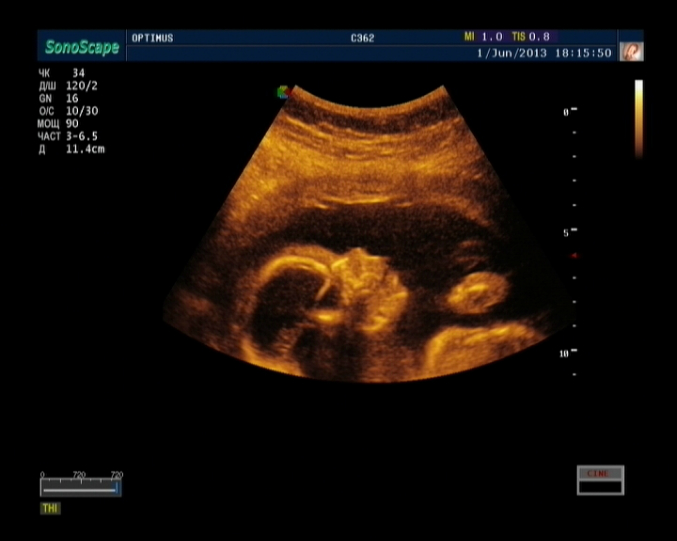

Результаты: УЗИ, КТГ, доплера, скринингаНу вот,наконец-то сходили мы на 3D УЗИ.Всё очень понравилось,делали почти час,всё рассказывали,показывали,малыш наш очень активный,постоянно барахтался,пяточку трогал,с пуповиной играл,видели как зевает,2 раза,так классно=))) Папе тоже очень понравилось=) Фото долго не получалось,да и не получилось как надо,малыш прятался=( И так,момент истины,у нас будет

МАЛЬЧИК!!=)))))))))))))))) Я так рада,сказали самец породистый,причиндалы хорошо показывает,так что не зря я на плановом УЗИ разглядела машонку=))

Разглядели,что губка верхняя как у сестренки=) С именем никак не определимся,муж сомневается в имени Тимур=(( Ну ниче,время еще есть,подумаем=))

Ну и вот наш сынок=))) Не знаю,разглядите или нет=)